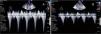

Quantification of dynamic gradients in the left ventricular outflow tract before (A) and after (B) discontinuation of dobutamine and administration of intravenous propranolol (1 mg/kg). The peak gradient in (A) is >64 mmHg with blood pressure of 90/60 mmHg; in (B) the peak gradient has fallen to 16 mmHg and blood pressure has risen to 110/70 mmHg.